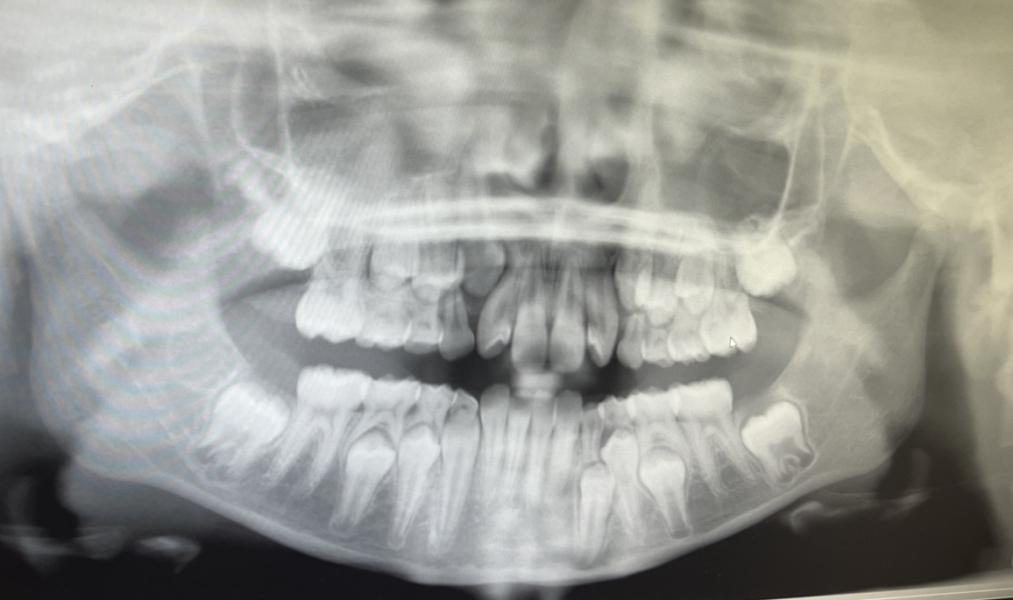

My DD is 12.5 now, she has lost 9 baby teeth & still has ALOT to go until orthodontist will put her on the waiting list for braces. I appreciate that you can’t do braces with baby teeth still in place & that NHS have a strict criteria but at what point would they be willing to remove some of the baby teeth to assist. For context, my daughter has only lost 1 baby tooth in the last 3.5 years! Her front adult teeth are extremely overcrowded due to the baby canines not falling out & the teeth aren’t able to turn to face forwards because of this. The dentist took X-rays and even the adult teeth underneath aren’t straight so what is the likelihood of them pushing the remaining baby teeth out naturally?? (Will upload pictures if anyone has similar experience with their own children)

They look to be developing fine to me. There is space for everything to move around ( it takes time) and all the teeth are present but most are quite a way off eruption.

Taking the baby teeth out now will not encourage the permanent teeth to erupt any quicker and you would risk the gaps closing up leading to a lot more crowding.

The last teeth to erupt will be her upper canines, after loss of the upper primary molars are lost. The primary molars take up approx 25% more room than the premolars that replace them which leaves adequate room for the canines.

The slightly rotated lateral molars are only partially erupted, once they are fully erupted the pressure from the tongue and lip muscles will derotate them.

@Hye000 when was the X-ray taken?

This X-ray was taken last year at her last orthodontist appt, she has another app in June.